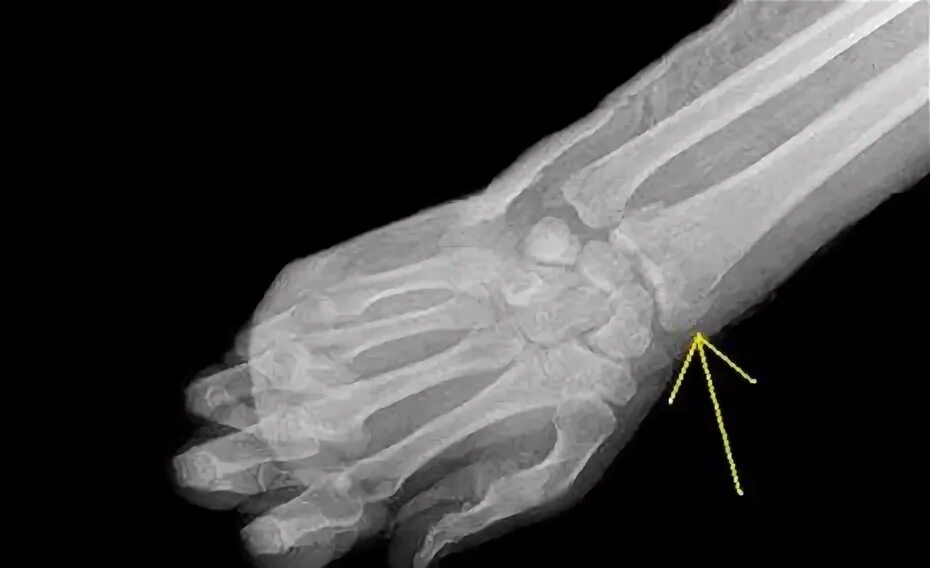

Смещение лучезапястной кости